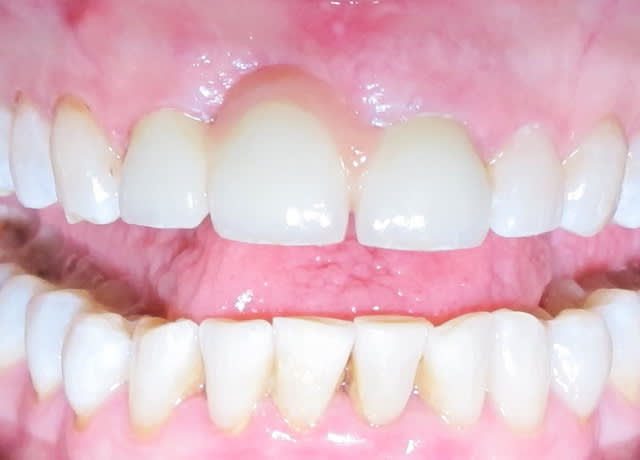

L'état paro du bas est super moche.

La 21 aurait du être allongée apicalement, elle est moins longue que la 12...

le problème ici sont les embrasures effectivement.

2 les dents sont assez peu hautes, on pourrait en profiter pour faire des élongations coronaires sur les incisives.

Ces 2 éléments conjugués auraient peut etre pu supprimer la ceram rose...

La 21 a été retouchée après la photo